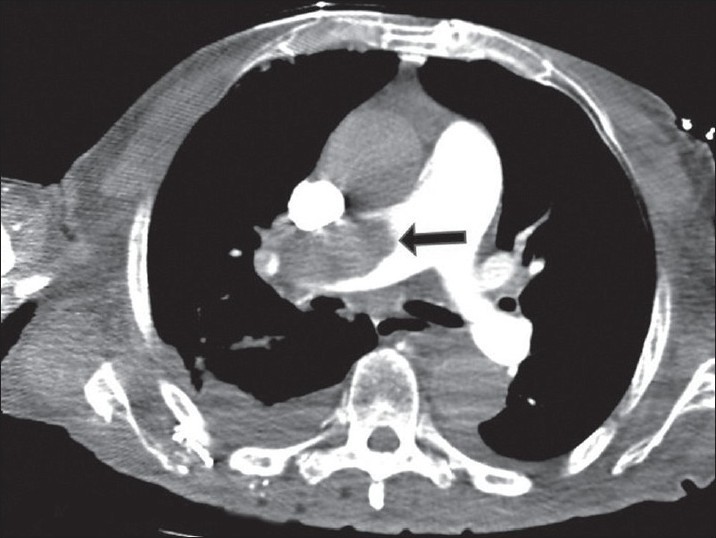

What is CTPA + what is it used for?

CT pulmonary angiogram Used to look for blood clots